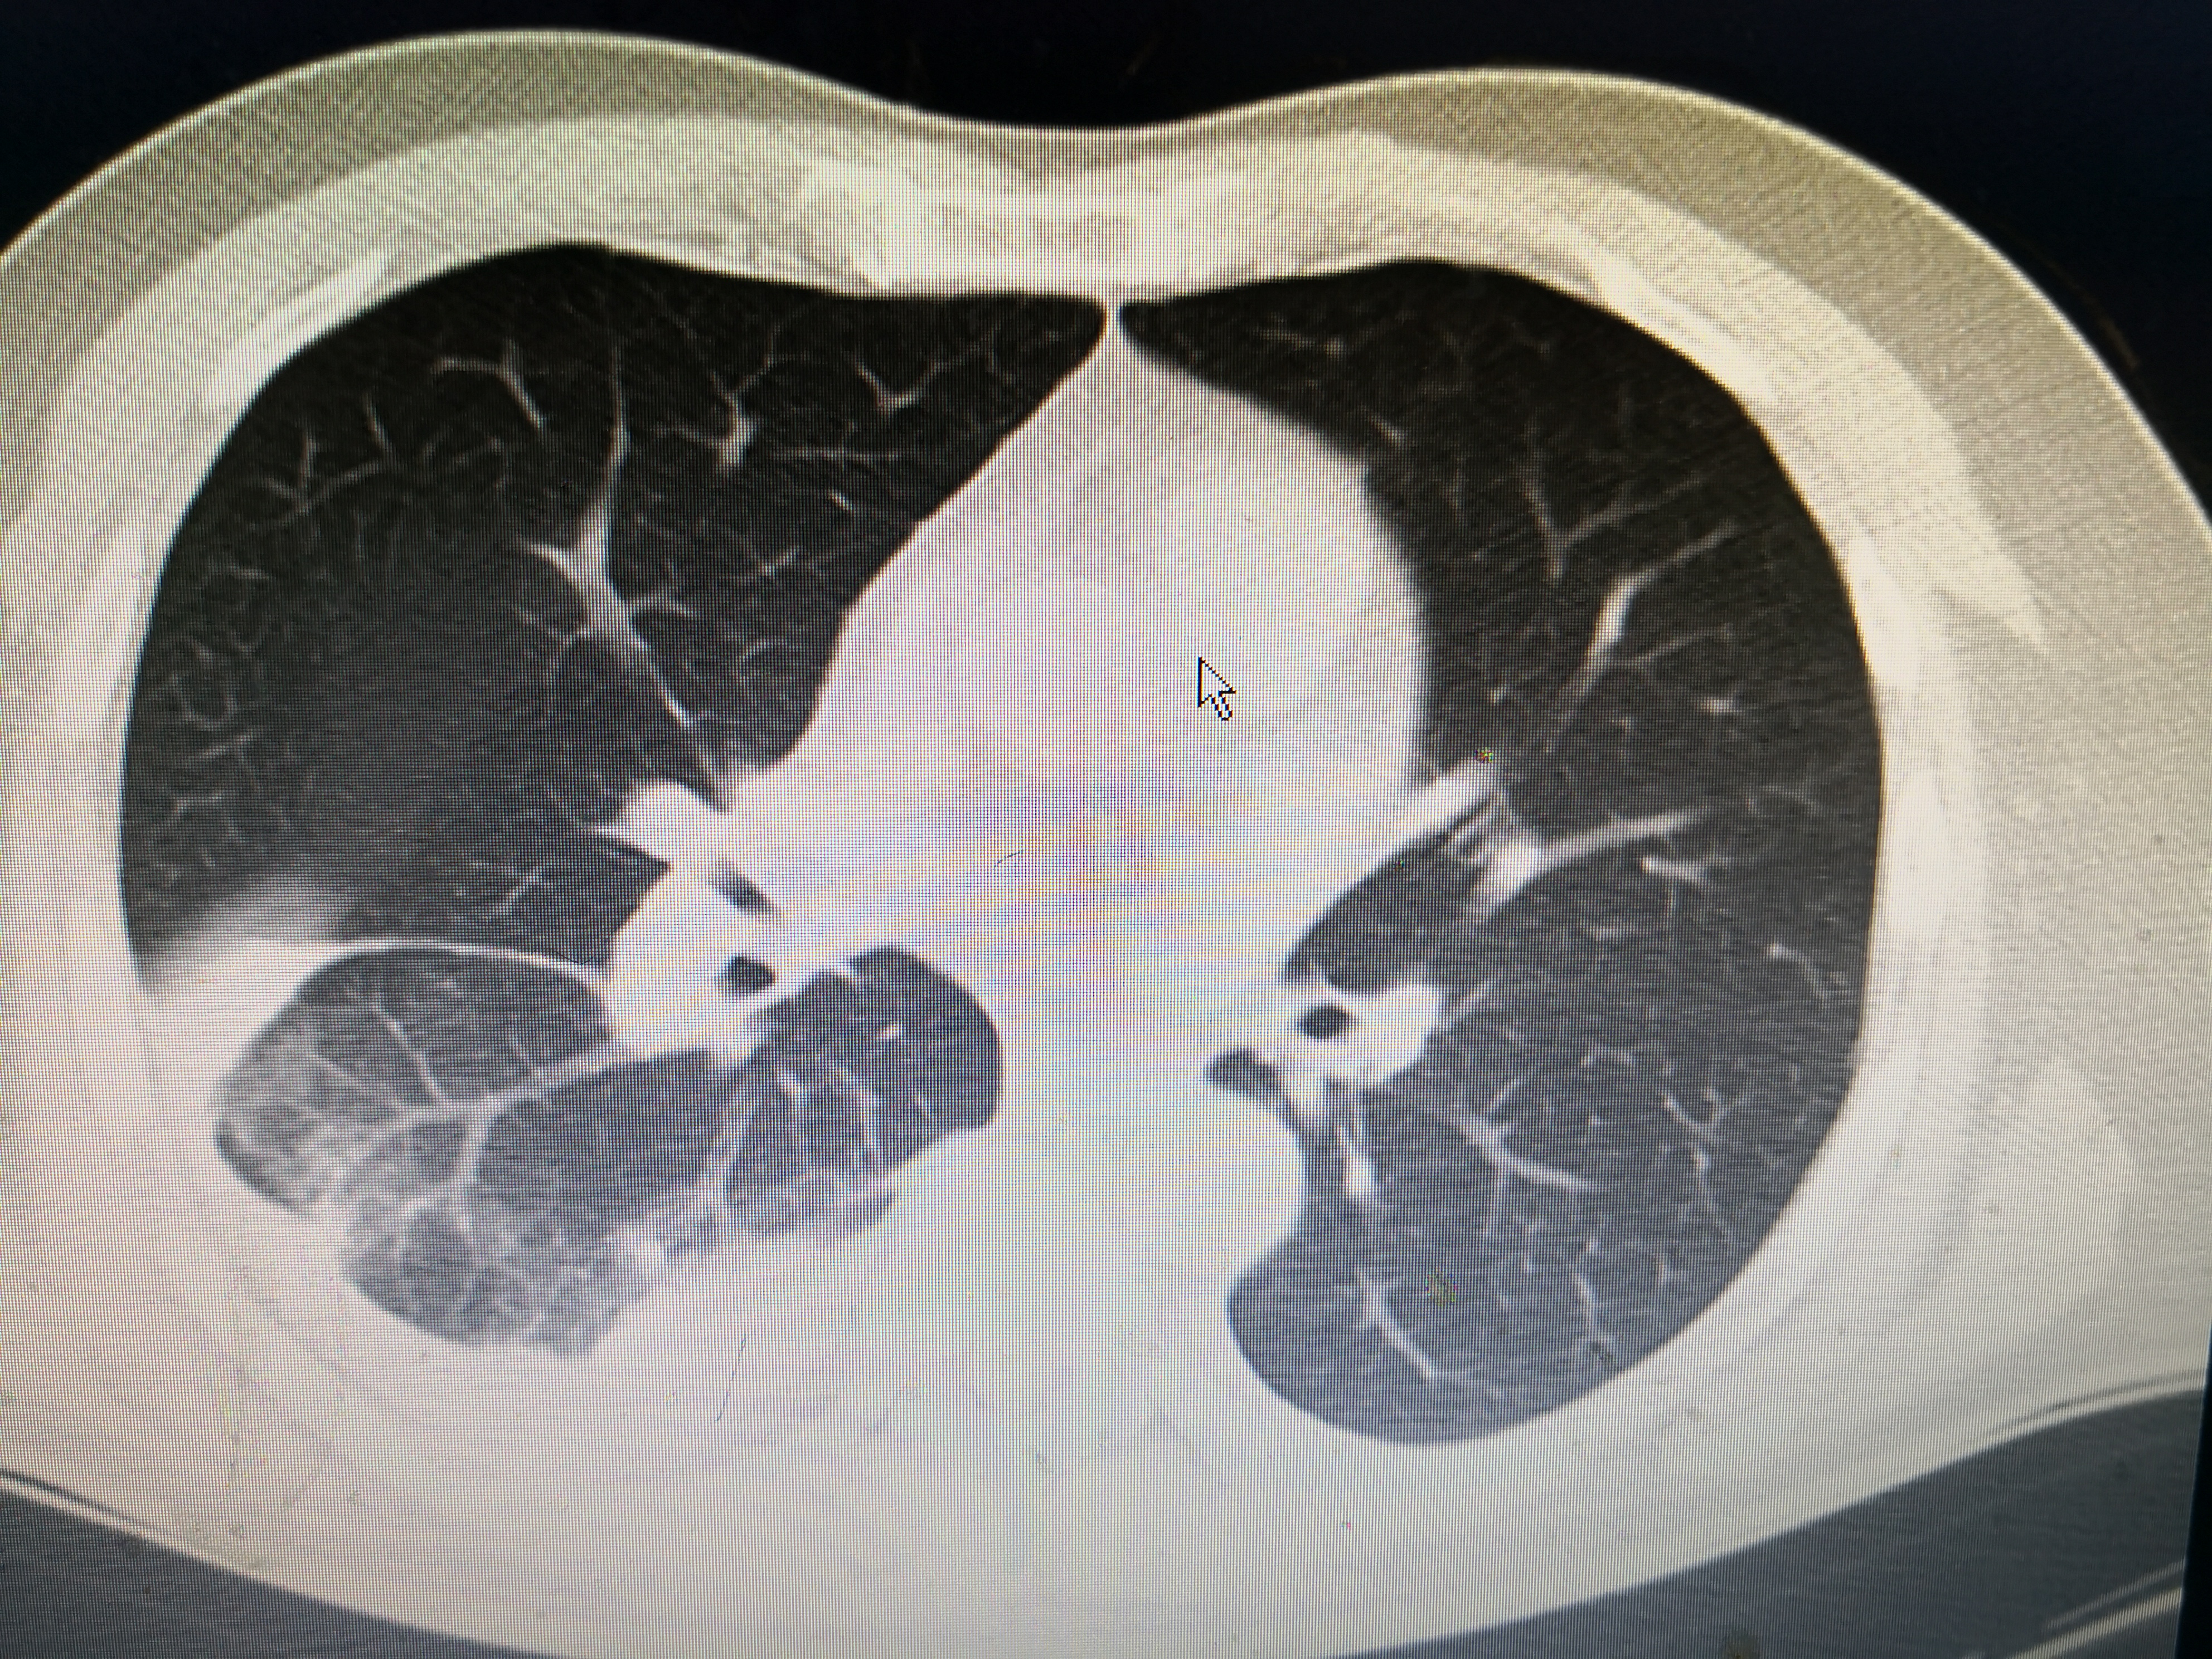

下面这个患者就是近期从西城院区转过来的发热,大片肺炎患者。患者男,55岁,因发热3天到西城院区就诊,体温最高41℃,伴有畏寒、乏力、纳差,咳嗽少痰,伴有顽固性呃逆,没有新冠肺炎流行病学史,但是CT提示右肺大片炎症,在发热门诊隔离抗炎,经两次筛查阴性,但是抗炎效果不佳,仍有高热,转到这边急诊二病区抗炎治疗。

该患者没有既往病史,没有新冠流行病学史,没有用药史,有典型的发热、咳嗽症状,CT提示右肺炎症。